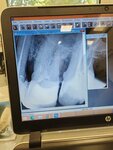

Dental clinic SV Apolloniya, Togliatti, photo